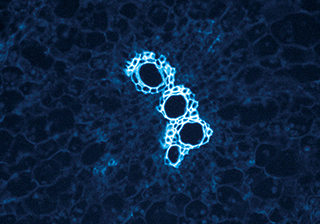

牛肺動脈內皮細胞 - MIchrome CMOS 相機

牛肺泡上皮細胞熒光成像-TrueChrome HDMI 相機

熒光成像 - TrueChrome Metrics